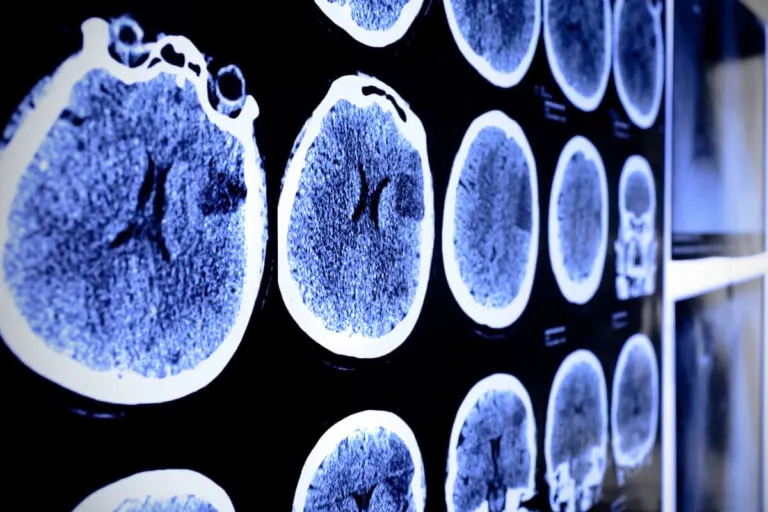

Pruebas de diagnóstico por imagen

El estudio imagenológico es vital para la identificación de las patologías tumorales a nivel del tejido cerebral. En general, la resonancia magnética (RM) es el más utilizado en el diagnóstico del astrocitoma.

La misma suele realizarse acompañada de medios de contraste que facilitan la ubicación del tumor y el establecimiento de un plan terapéutico.

- Tomografía computarizada (TC).

La biopsia por aguja forma parte crucial del diagnóstico definitivo de un tumor cerebral. La misma puede realizarse de forma guiada por resonancia magnética o por tomografía computarizada. La muestra obtenida debe ser enviada al especialista patólogo.

Los estudios microscópicos permiten la estadificación o gradificación del astrocitoma con el fin de establecer un pronóstico y definir la conducta terapéutica con el paciente.